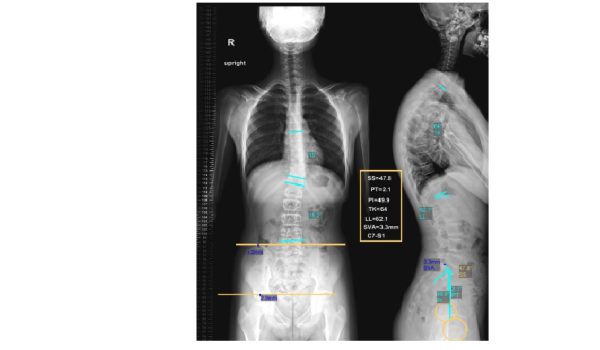

رادیوگرافی انحراف ستون فقرات Full spine با دستگاه جدید و روز دنیا 2024 و کاملا اتوماتیک: آدرس: تهران ،تقاطع بلوار کشاورز و کارگر،نبش کارگر ،طبقه فوقانی بانک ملی ساختمان 193 تلفن:…